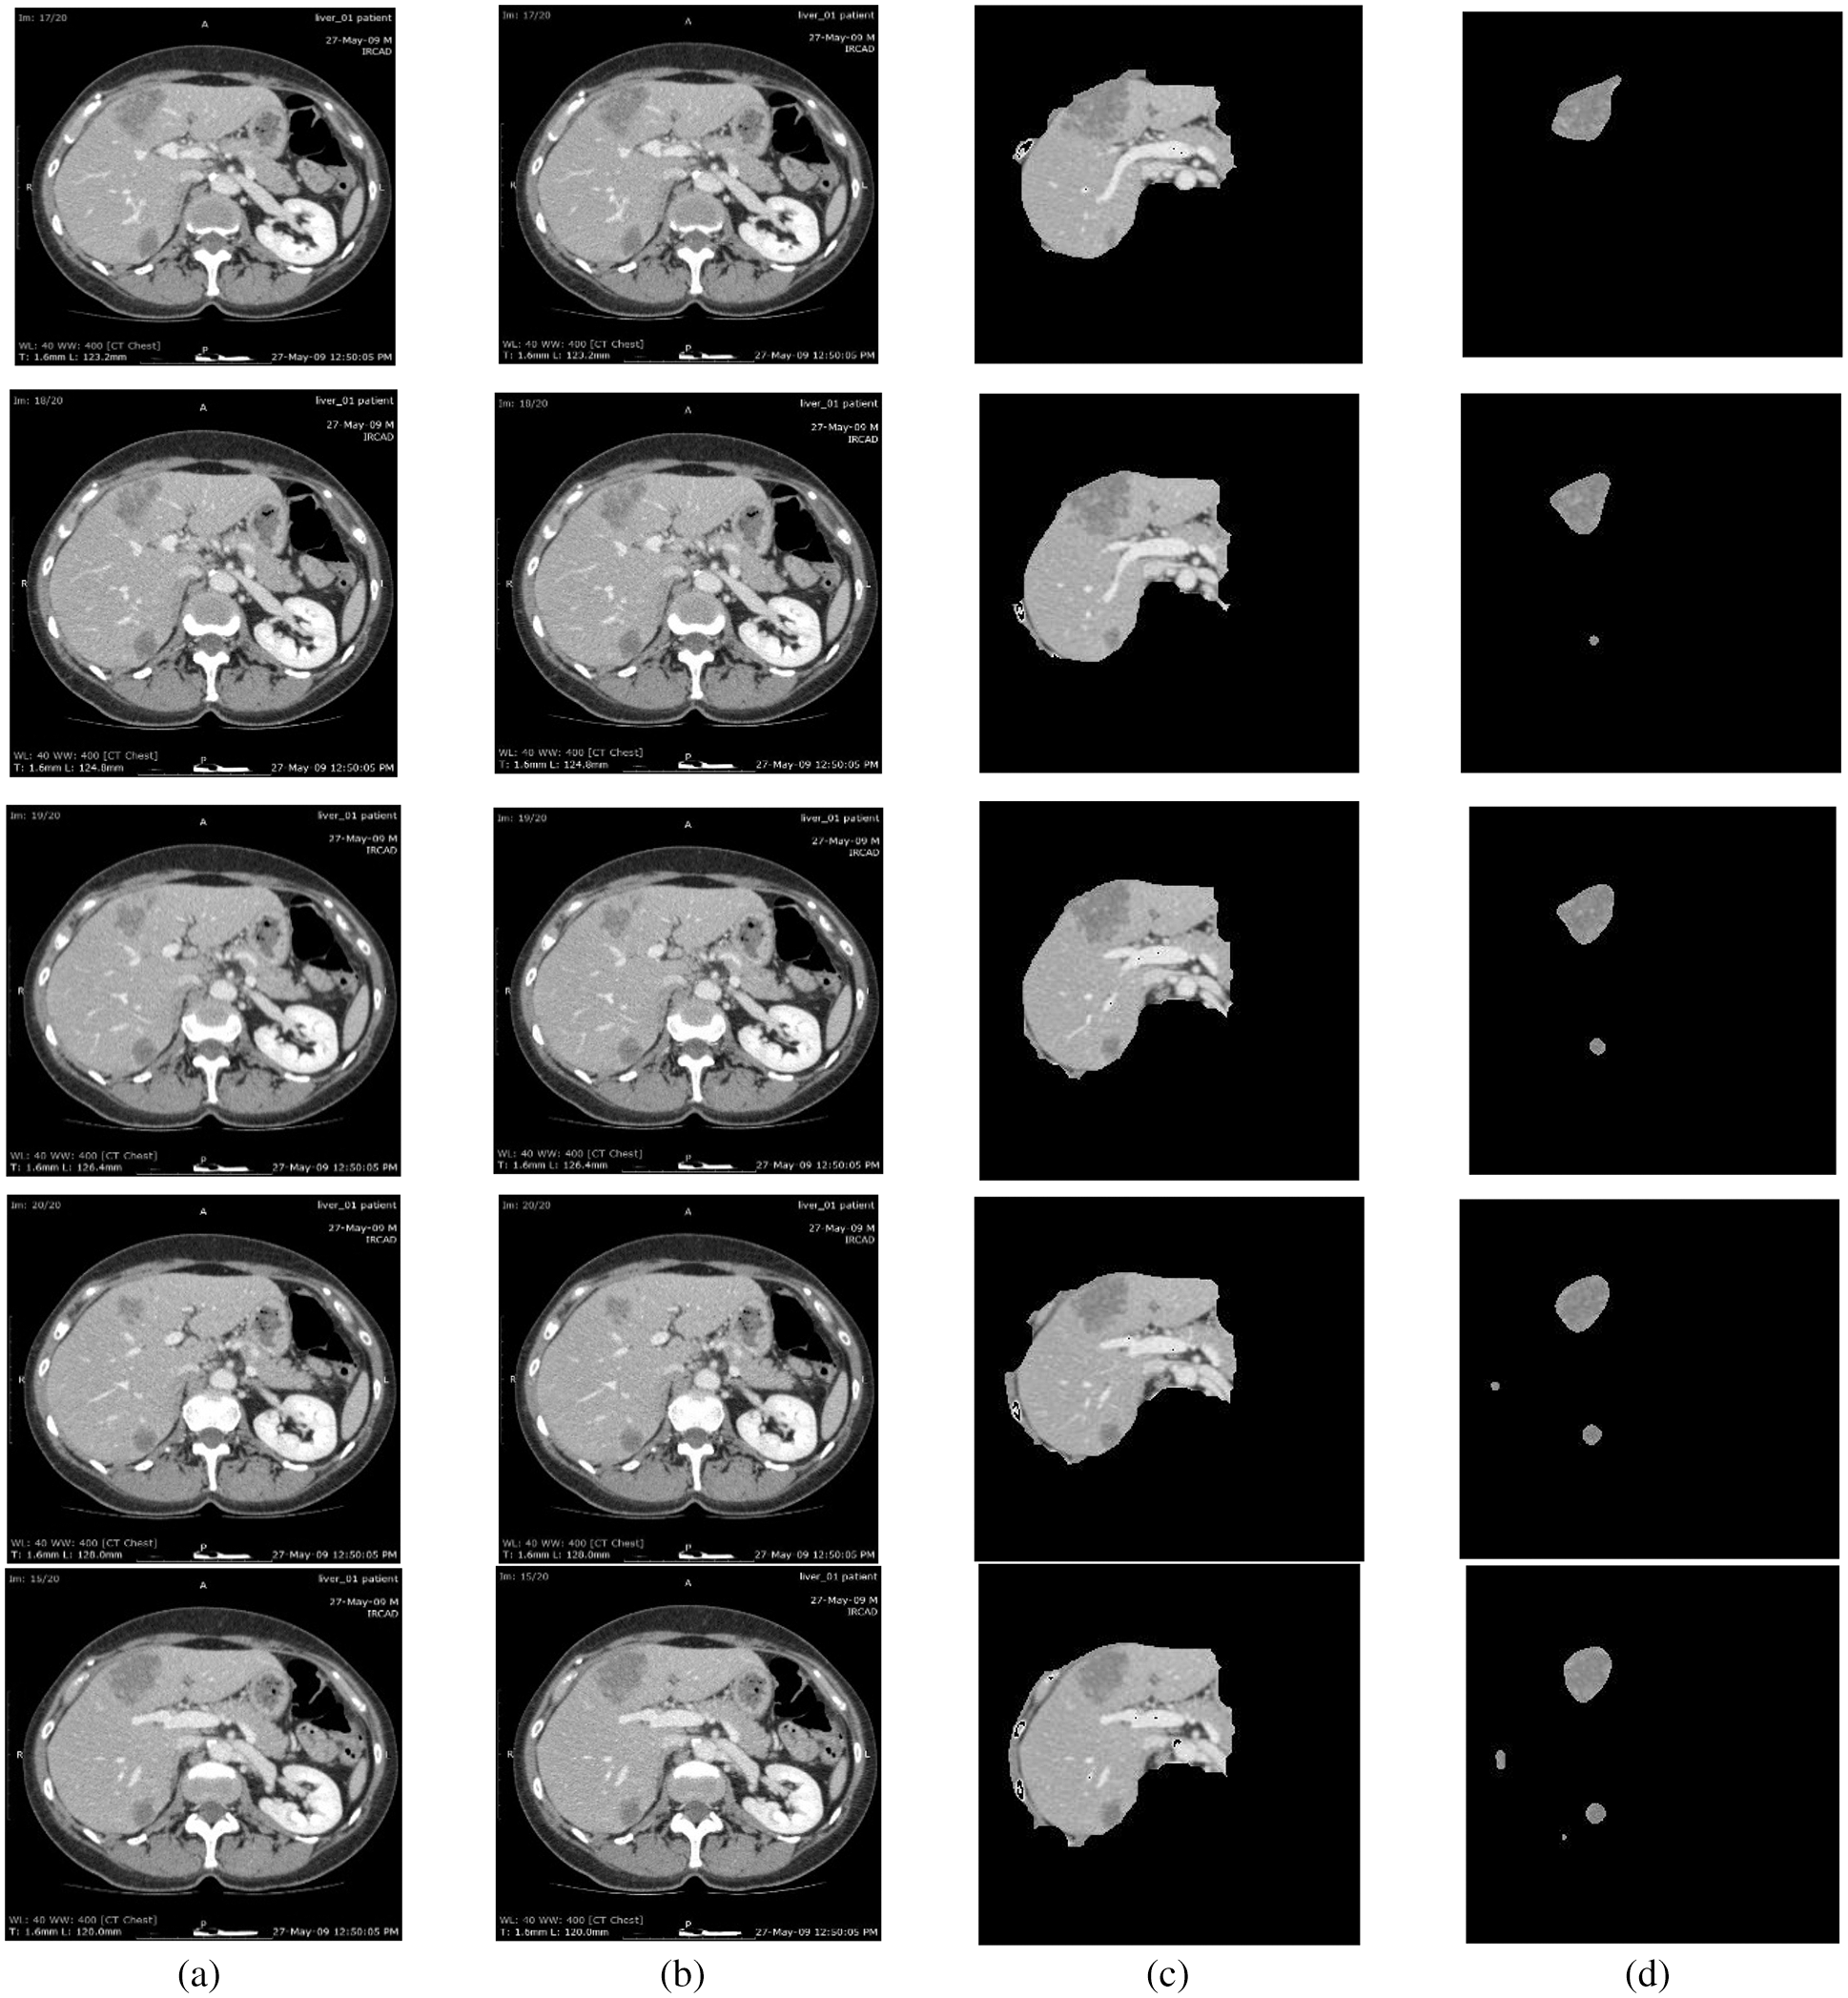

For this purpose, CE using NLMT is applied in this work. Figs. 2 and 3 show the proposed techniques’ segmentation results for the sample of 20 images in the public 3DIRCADB dataset (Figs. 4 and 5) (Tabs. 1 and 2).

Figure 2: Segmentation results of 3DIRCADB public dataset: (a) Input image (b) processed output using CE using non-linear filtering (c) the output of AEM with CED algorithms (d) output of MAT-ACM

Tab. 1, Figs. 2 and 3 show that the AEM with the Canny technique provides better performance results than the other existing traditional techniques. The mean VOE (6.92) and execution time (30 s) of AEM with Canny method is comparable with the existing methods (Li et al. 2013; Li et al. 2015 and Shi et al. 2016). Based on the qualitative, quantitative and comparative performance results, the most appropriate segmentation technique is identified, and its resultant image is considered for the following tumor segmentation process. The performance evaluation shows that the AEM with the Canny operator provides increased segmentation results for both empirical datasets.

The LTS is developed by implementing different FAS techniques. In experiments, the proposed and existing ST results are evaluated based on qualitative and quantitative analyses. Public 3DIRCADB and non-public datasets are used, and the resultant images from applying each ST are evaluated in the qualitative analysis. In the quantitative analysis, the performance of the techniques are analyzed using various performance measures. An AEM with a CED model is implemented, which increases the convergence speed of the iterative process for decreasing the Volumetric Overlap Error VOE (6.92%) values compared with the traditional techniques. The significant advantages of this technique are that it can detect the edges even in noisy environments and provide accurate positioning. So, the resultant image of AEM-CED is considered as the input for the LTS system. So, the MAT-ACM technique is implemented for accurate LTS. This technique follows the texture-based model, providing decreased VOE (3.08%) values than the existing methods and shows flexibility during segmentation.